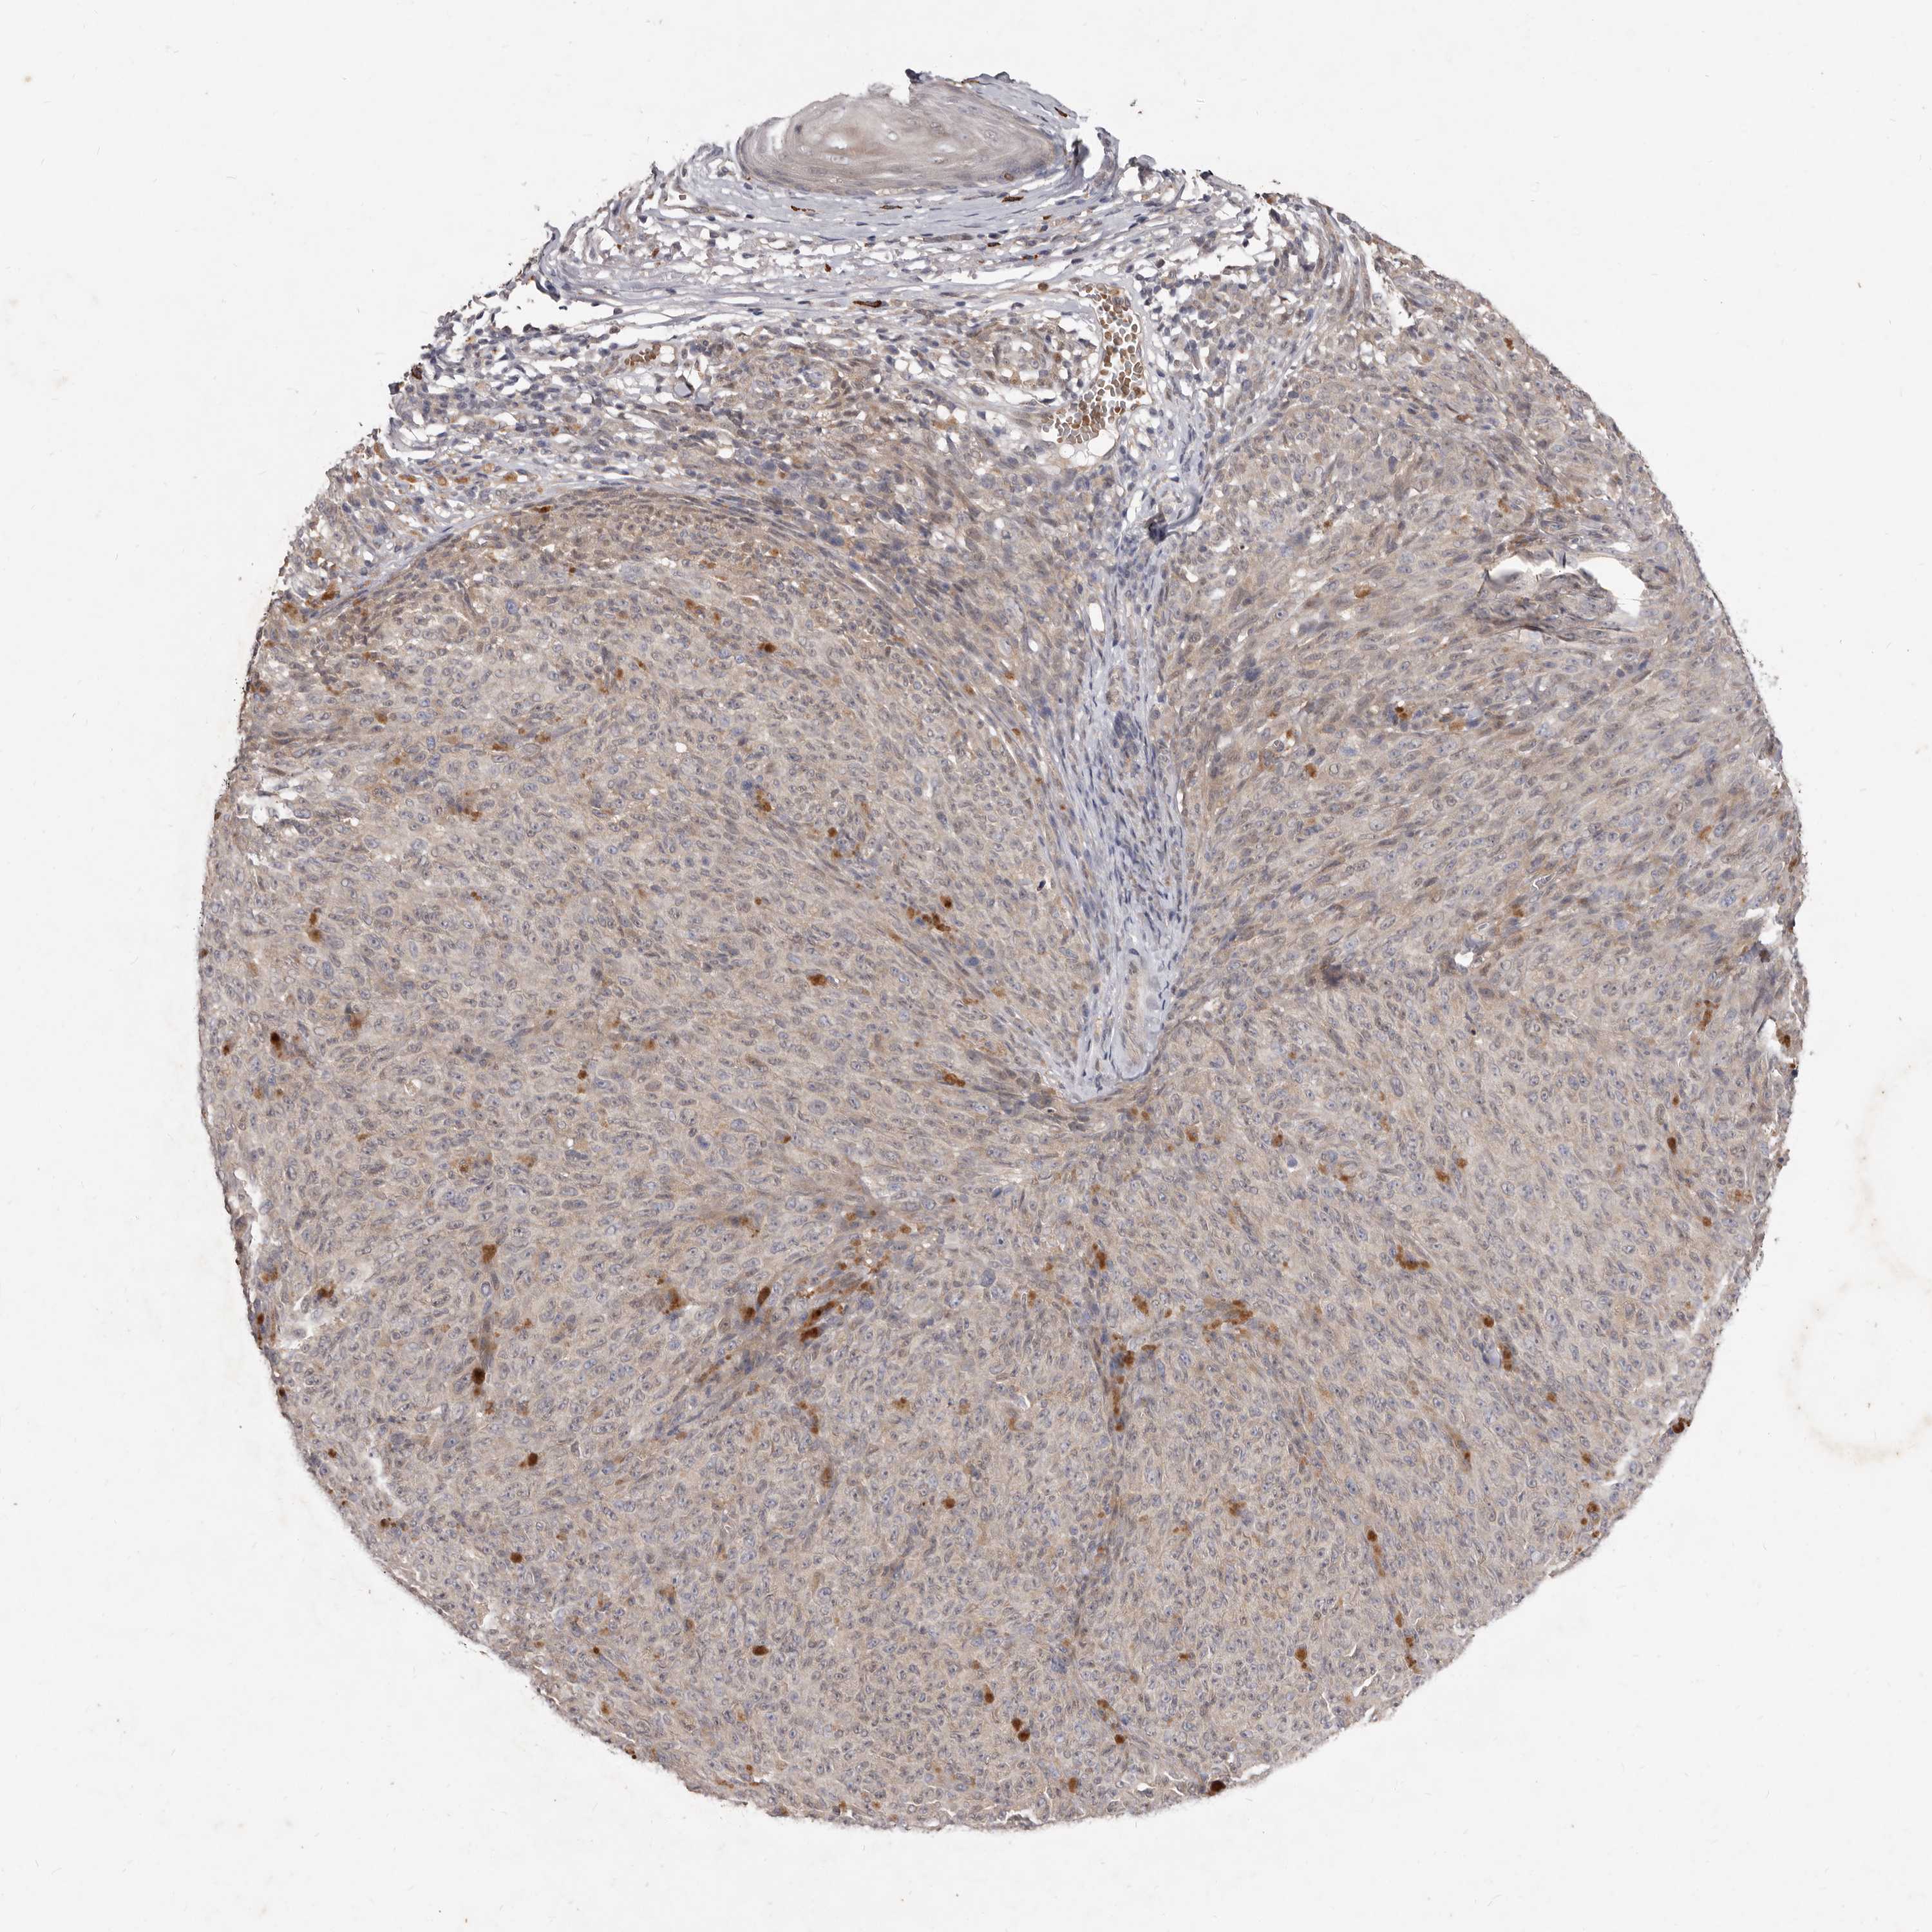

MELANOMA - Protein expressioni

A mouse-over function shows sample information and annotation data. Click on an image to view it in a full screen mode. Samples can be filtered based on level of antibody staining by selecting one or several of the following categories: high, medium, low and not detected. The assay and annotation is described here.

Note that samples used for immunohistochemistry by the Human Protein Atlas do not correspond to samples in the TCGA dataset.

Antibody stainingi

Antibody staining in the annotated cell types in the current human tissue is reported as not detected, low, medium, or high, based on conventional immunohistochemistry profiling in selected tissues. This score is based on the combination of the staining intensity and fraction of stained cells.

Each image is clickable and will lead to virtual microscopy that enables deeper exploration of all samples and also displays staining intensity scores, fraction scores and subcellular localization as well as patient and tissue information for each sample.

HPA022434

HPA022953

HPA022959

HPA028758

CAB007783

Staining

High

Medium

Low

Not detected

Intensity

Strong

Moderate

Weak

Negative

Quantity

>75%

75%-25%

<25%

None

Location

Nuclear

Cytoplasmic/membranous

Cytoplasmic/membranous,nuclear

Malignant melanoma, NOS

Malignant melanoma, Metastatic site